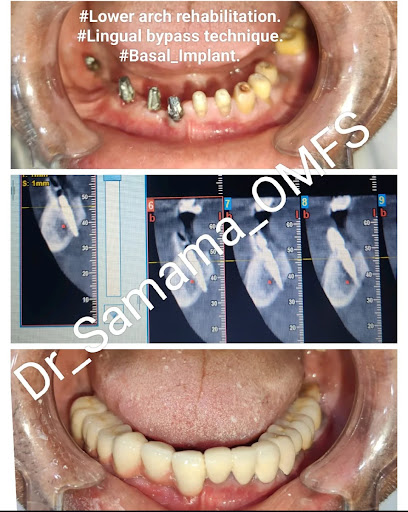

Gallery